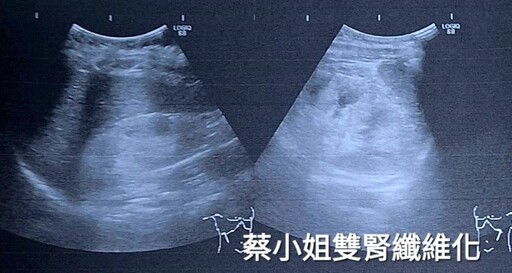

年僅28歲從事金融業、同樣有糖尿家族史的蔡小姐,未成年就確診糖尿病,近期因為情緒困擾以致飲食無節制,體重肥胖級,不但血糖失控又忽視門診追蹤,在高血壓、嚴重水腫、啤酒尿情況下就醫檢查,報告也顯示必需洗腎的結果!